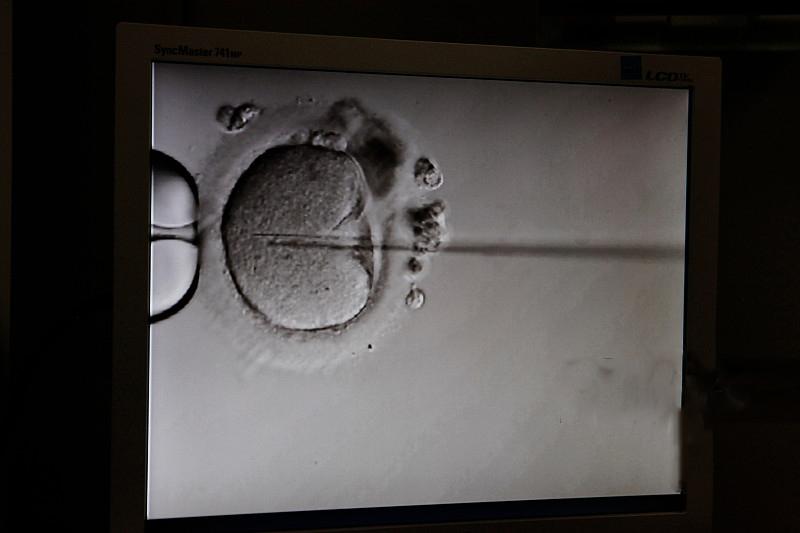

受精的精子通常是高质量的精子。男性一次的射精量在2-5ml左右,一般包含数千万到上亿个精子。而且最后能达到受精部位的精子只有亿万分之一,因此是最好的精子。精卵结合需要综合因素,不仅要有良好的精子质量,而且要与卵细胞排出的时机紧密配合。因此一定要在排卵期内射精,这样才有可能结合成受精卵。